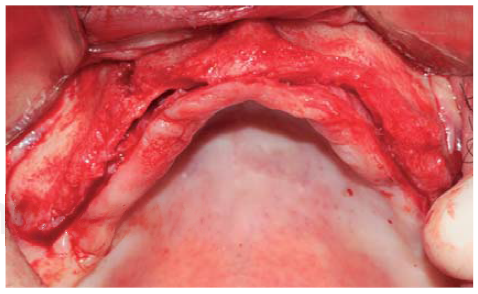

A full thickness incision over the crest was performed, raising a mucoperiosteal flap exposing bone table up to 4 mm from the top of the crest in vestibular direction; from that point the flap was divided into partial thickness (Figure 3). After this, impact points were marked in designated places according to surgical guide for implant placement; perforations were initiated with a 1.6 mm diameter burr in order to determine desired implant depth and axis. After this, a ridge was created on the crest with a diamond burr, fracturing cortical bone to create chisel's access to cancellous bone, and with the aforementioned, bone tables were separated until reaching a 5 mm depth (Figures 4 y 5). Perforations were further continued with a 2.0 diameter burr (Figure 6), and vestibular table expansion was undertaken creating greenstick fracture with the expanders, until reaching sufficient osseous bed diameter (3.2 mm diameter) (Figures 7 y 8). Implants were then placed at a 25 rpm speed and 35 Nem torque (Figures 9 y 10). After this, a particulate bovine bone graft was placed (Bonefill® Bionnovation Biomedical, Sao Paulo, Brazil) with the aim of preserving integrity of vestibular bone tables (Figure 11). All these procedures were repeated for placement of all six implants. Finally, sutures were undertaken with monofilament nylon 5/0.

Figure 4 Diamond disc (0.5 mm thick) used to create a crest groove passing through cortical bone and allowing access for bone chisel.